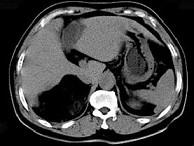

问题 男,59岁,右侧腰背酸痛,CT检查如图所示,应诊断为()

选项 A.右肾上腺腺瘤 B.右肾上腺转移瘤 C.右肾上腺髓样脂肪瘤 D.右腹膜后脂肪瘤 E.右肾血管平滑肌脂肪瘤

答案 C